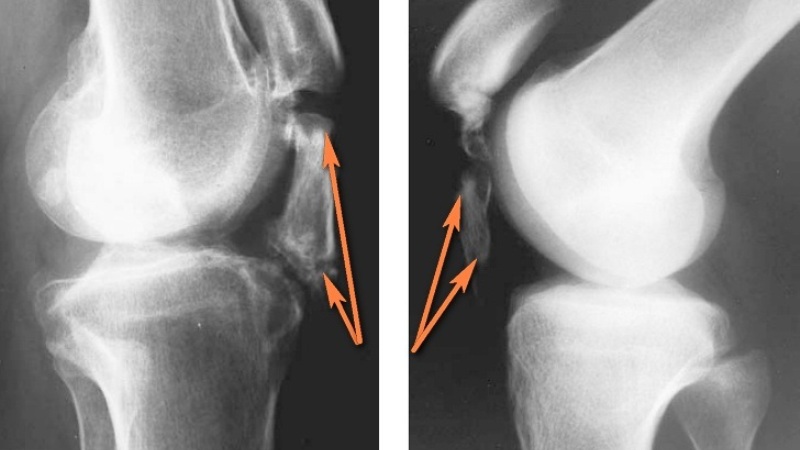

- Для уточнения характера и степени повреждения лечащий врач назначает методы инструментальной диагностики: рентген, ультразвуковое исследование, компьютерную или магнитно-резонансную томографию.